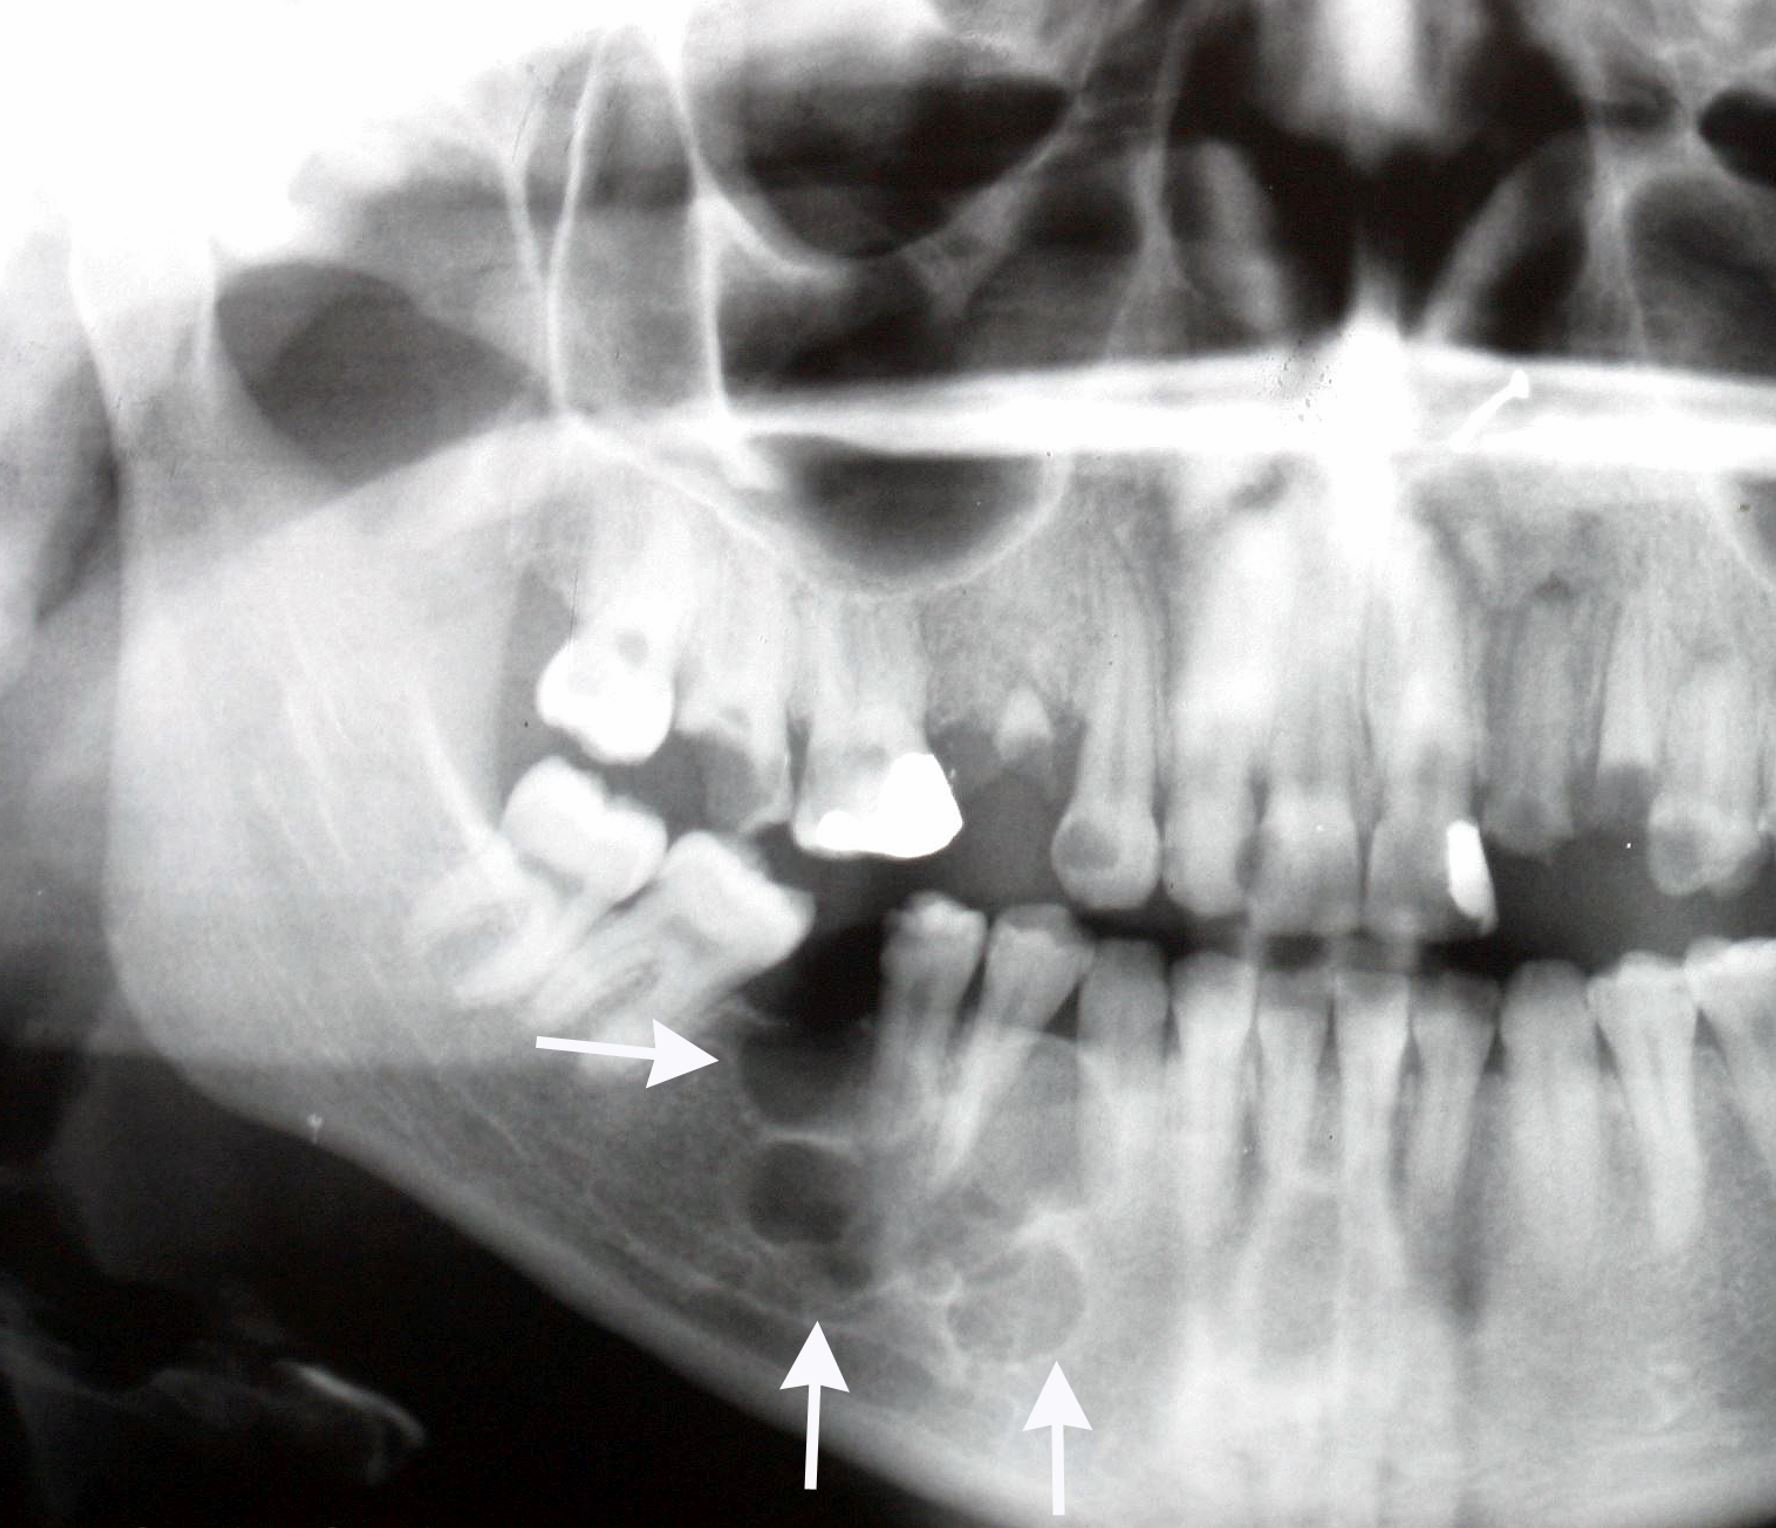

Radiology description

- Ameloblastoma, conventional

- Expansile multilocular radiolucency, well defined, corticated border

- Some cases exhibit classic soap bubble appearance

- May or may not be associated with impacted tooth / teeth

- Resorption or displacement of tooth roots

- Reactive bone formation may occur, most commonly in desmoplastic ameloblastoma, which may resemble a fibro-osseous lesion radiographically due to the presence of osteoplasia

- May have a unicystic radiographic appearance on plain images; requires microscopic examination for distinction from ameloblastoma, unicystic type (Dentomaxillofac Radiol 2018;47:20170288)

- Ameloblastoma, unicystic type

- Unilocular radiolucency, well defined, corticated border

- Often associated with an impacted tooth, specifically mandibular third molar

- Root resorption may occur

- Cortical perforation in 33% of cases

Radiology images